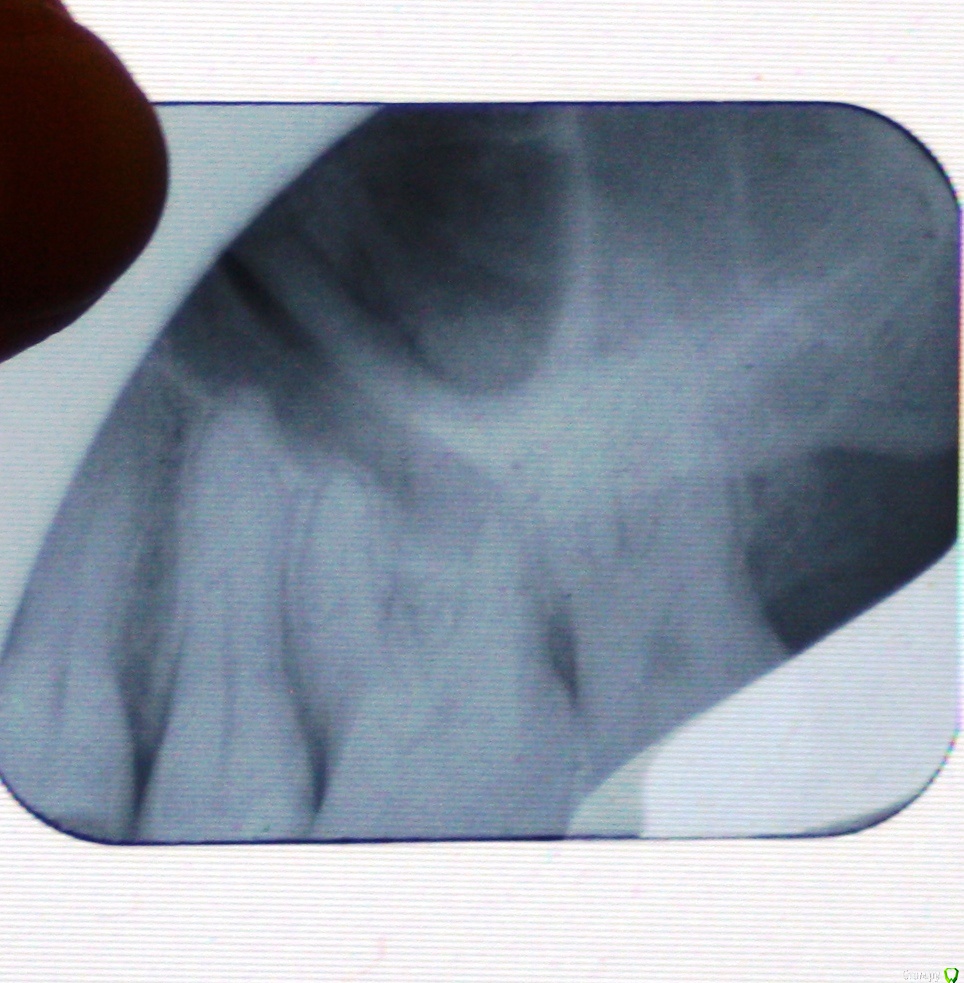

АннаВ555 Опубликовано 8 декабря, 2017 Автор Поделиться Опубликовано 8 декабря, 2017 Еще раз прикрепляю, это зуб который четвертый слева от двух передних зубов. 1 Ссылка на комментарий

___49___ Опубликовано 11 декабря, 2017 Поделиться Опубликовано 11 декабря, 2017 (изменено) Еще раз прикрепляю, это зуб который четвертый слева от двух передних зубов. IMG_0249.JPGНа снимке у вас 7\6\5\4 зубы , 4ка -похоже , что у апекса определяется участок деструкции костной ткани , зуб требует эндодонтического лечения. Но .... ваш снимок обрезан, и всей картины не видно(могу и ошибаться), потому - переснять, и только после этого делать объективные выводы. Изменено 11 декабря, 2017 пользователем ___49___ Ссылка на комментарий